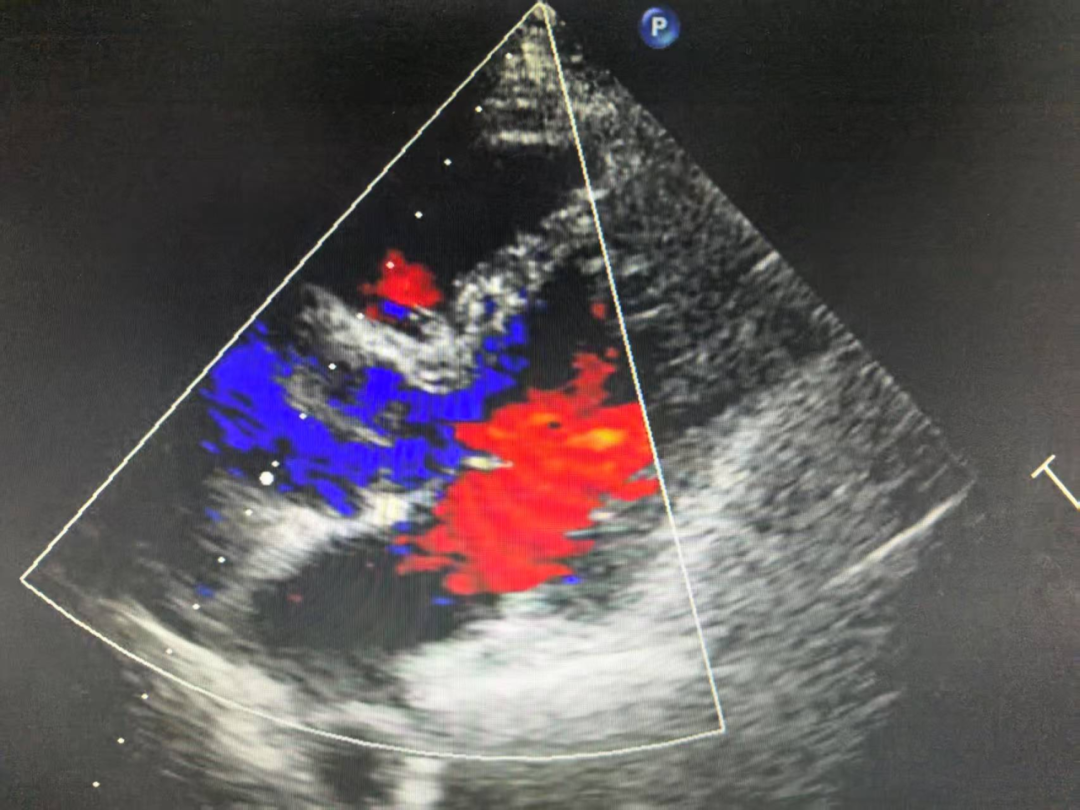

10月14日,彭磊因身体极度不适,状态极差,被家人紧急送往医院,并直接送入ICU接受救治。通过心脏彩超检查发现,心功能EF值急速下降到26%(正常值在50%-70%左右),随后更是跌至10%,肝肾相继衰竭。在当地医院,他不得不依靠ECMO(体外膜肺氧合技术)、IABP(主动脉内球囊反搏)和CRRT(血液净化)三台“救命机器”维持生命体征。

其间,通过血液检测,医生已明确彭老师患上的是病毒性心肌炎,心肌损伤极其严重。然而,经过连续多天的抢救,彭老师病情仍在恶化,心功能EF值下降到10%左右,出现了心脏扩大、心力衰竭的临床征象,必须依赖机械辅助维持心脏的跳动。

11月5日,手术如期进行。植入左室辅助装置(LVAD)后,彭磊的心脏开始与人工心脏"分工合作",各负担50%的泵血工作。更令人欣喜的是,原本衰竭的右心功能竟随之恢复,他顺利脱离了所有辅助设备。